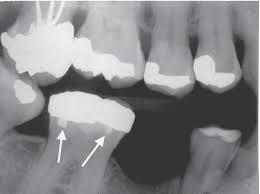

Radiopaque or Radiolucent

PDL

radiolucent

lamina dura

radiopaque

alveolar bone proper

amalgam restorations